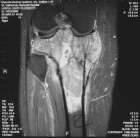

Case 8

M.L. - 44 year old female presents with seven month hx of right knee pain.

Zoom image: Radiological image Radiological image.